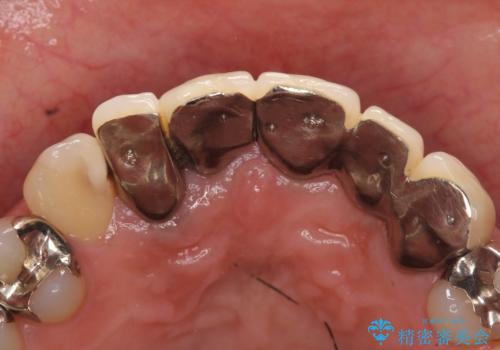

- 昔入れた被せ物と歯茎の間の隙間が気になると来院された方の症例です。

右上1、2番目の歯と左上1、2、3、番目の歯のブリッジを除去し、オールセラミッククラウンによる補綴を行うことで見た目を改善しました。